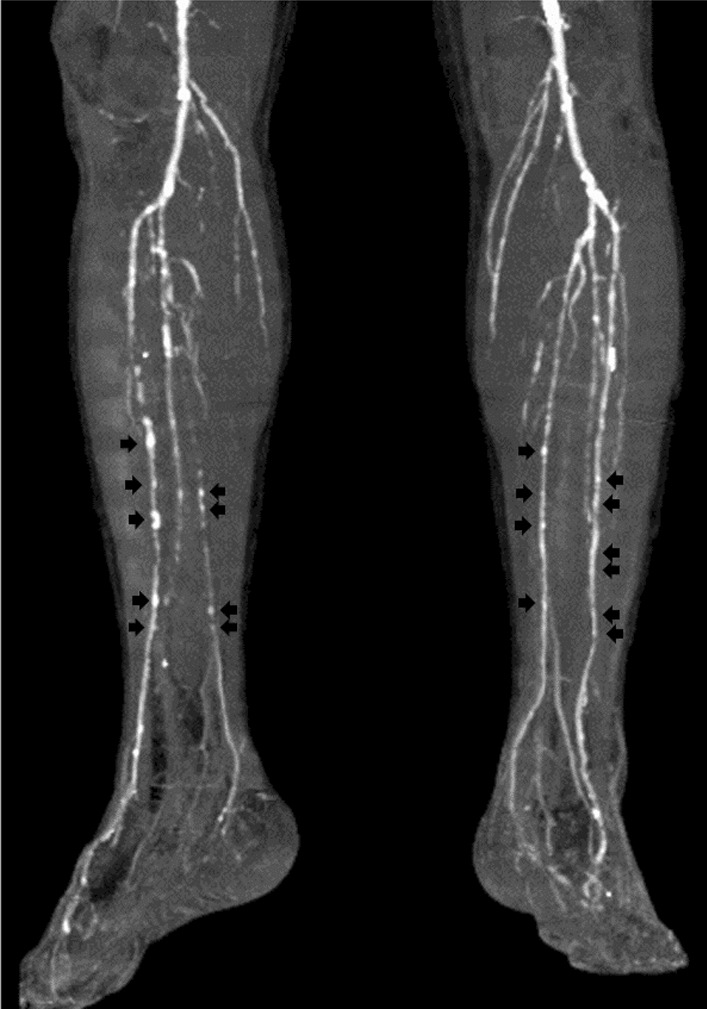

Fig. 3.

Computed tomography of the lower legs. Axial images of plain computed tomography showed severe calcification of infrapopliteal arteries in the bilateral lower legs

Fig. 6.

Computed tomography of the lower legs showing spotty calcification in the bilateral infrapopliteal arteries (black arrows)